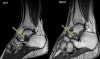

T1 MRI : 족근동 증후군(Sinus tarsi syndrome)

왼쪽 : 족근동에서의 정상적인 지방 소멸로 인해 저강도로 나타남

오른쪽 : 정상적인 영상